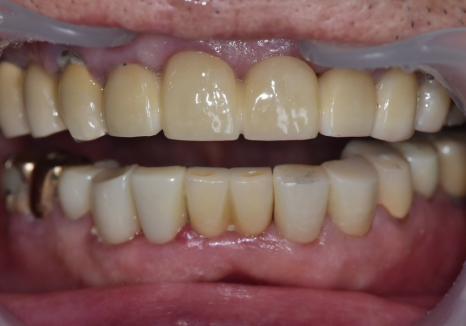

240502

보철물을 올릴 때는

음식물이 최대한 끼지 않도록

정밀하게 설계하는 데 집중했습니다.

크라운 세팅 시에는 치간 칫솔 사용법을

상세히 설명해 드리며

관리 방법도 잊지 않고 안내해 드렸어요~

240711

치료가 마무리된 후의 모습입니다.

검게 변색되었던 부분들이 사라지고

인상이 전체적으로 깨끗하고 단정해 보이네요.^^

240223(전) 240711(후)